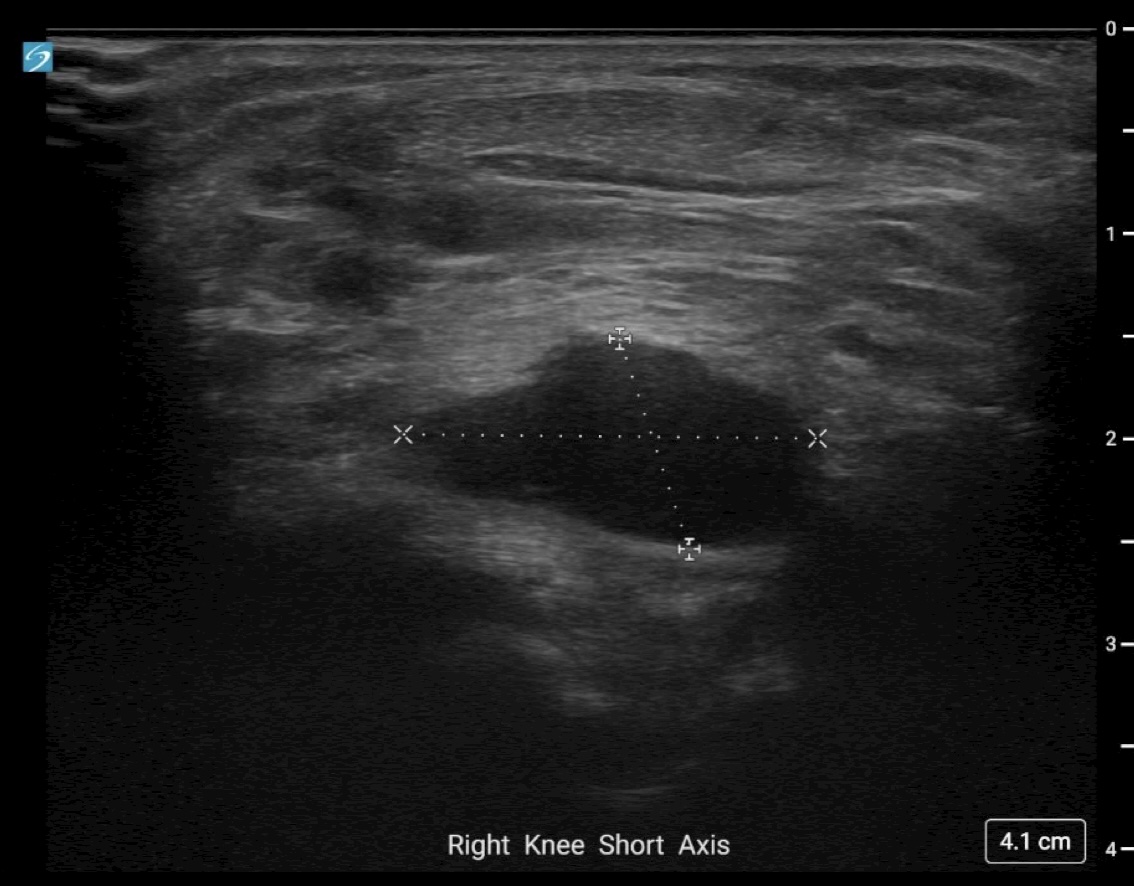

Image Interpretation: An anechoic, well-circumscribed, well-demarcated mass was noted deep to the infrapatellar fat pad. This measured 2.02 cm x 1.08 cm x 1.72 cm. No color Doppler flow was noted and the structure remained noncompressible when pressure was applied. A separate, smaller, anechoic mass was noted deeper to this structure and likely communicated with it. Findings were consistent with a multiloculated cyst of intra-articular origin.